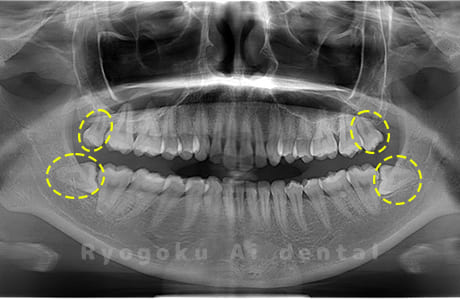

Case02

- 原因

- 下顎の水平埋伏智歯

- 治療内容

- 下顎の水平埋伏智歯を抜歯

<リスク・副作用>

手術後は痛み、腫れ、痺れなどの副作用が生じる場合があります。